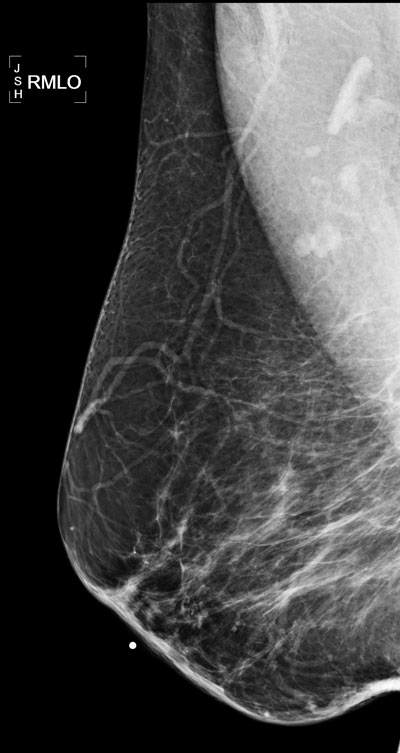

The density of the breasts in this mammogram is consistent with the patients age seen by the fact that most of the dense tissue seen in younger people has been replaced by fat which appears black on the mammogram.

There are a few scattered calcifications widely spread throughout image, but no cluster of calcifications so not very suspicious.

There is a skin marker in image one and two. The marker is placed around skin lesion to ensure that it is not mistaken for breast lesion.

You can also see few lymph nodes in the second image in axilla. Small nodes are normal just like nodes in inguinal region.